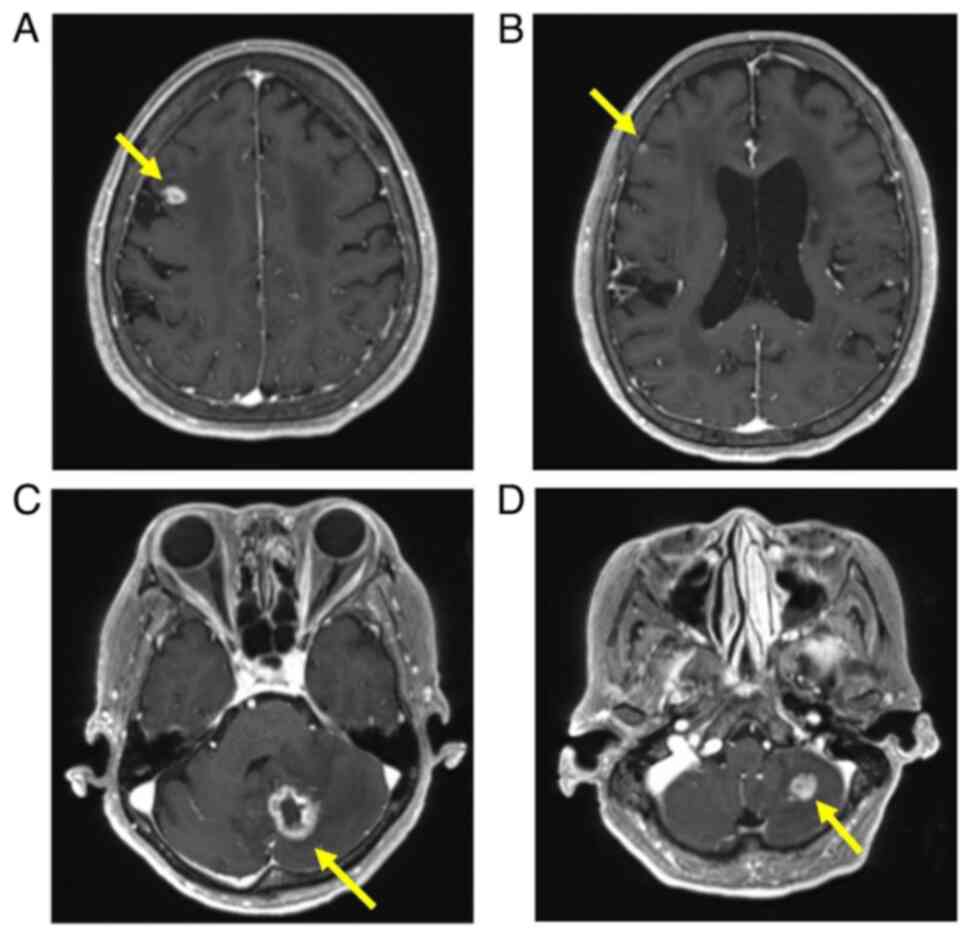

Methotrexate‑related other iatrogenic immunodeficiency‑associated lymphoproliferative disorder (MTX‑OIIA‑LPD) is prone to extranodal involvement but rarely involves the central nervous system (CNS). The present study reports a case of MTX‑OIIA‑LPD of the CNS discovered during medication‑related osteonecrosis of the jaw (MRONJ) treatment in a 76‑year‑old woman with rheumatoid arthritis (RA). The chief complaint of the patient was bone exposure and pain in the right mandibular molar. The patient had been receiving MTX for RA and alendronate sodium hydrate for osteoporosis, followed by denosumab. Treatment was initiated based on a diagnosis of MRONJ. However, the patient experienced lightheadedness and floating dizziness afterwards. Examinations revealed scattered neoplastic lesions in the brain. The histopathological diagnosis was diffuse large B‑cell lymphoma. A systemic search also revealed adrenal involvement. Since the patient was taking MTX, a diagnosis of MTX‑OIIA‑LPD was made and MTX was discontinued. Chemotherapeutic agents were administered since the central lesions became symptomatic. The MTX‑OIIA‑LPD lesions in the brain and adrenal glands completely resolved 8 months after onset. The physical condition of the patient improved, and the bone‑exposed areas became epithelialized. Reports on MTX‑LPD in the oral and maxillofacial region are few, which may delay its diagnosis. Therefore, biopsy of oral lesions in patients with MRONJ who are taking MTX and collaboration with related diagnostic departments, such as rheumatology and hematology, must be done to initiate the diagnosis and treatment of extraoral MTX‑LPD.